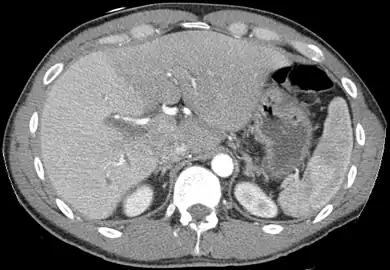

MDCT image. 3D image created by MDCT can clearly visualize the liver, measure the liver volume, and plan the dissection plane to facilitate the liver transplantation procedure.

Phase contrast CT image. Contrast is perfusing the right liver but not the left due to a left portal vein thrombus.